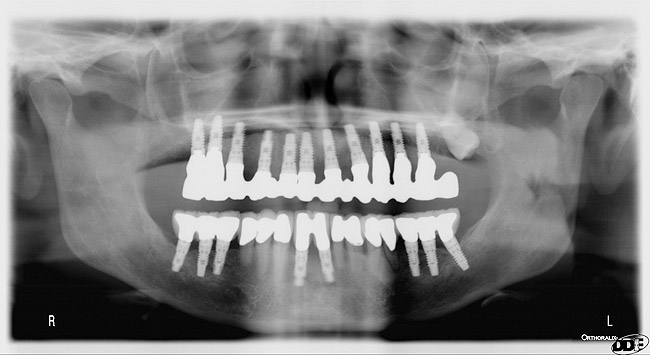

Figure 12  Post-placement panographic revealing implant positions.

Figure 12

A DFDBA bone-graft putty (Regeneform) was used to graft the entire maxillary arch. All extraction defects were degranulated, the bone was decorticated to allow bleeding, then the DFDBA putty was placed and covered with resorbable collagen membranes (Biomend Extend, Zimmer Dental) (Figure 5). Primary closure was obtained and the patient wore her denture after a soft reline for a period of 6 months (Figure 6). At 6 months post-graft, a CBCT scan revealed substantial graft material from both an axial (Figure 7) and a crosssectional view, showing more than 15 mm of bone height (Figure 8). The 3D view from the CBCT also showed substantial ridge changes in both height and width (Figure 9). Using a CBCT software program (SimPlant, Materialise Dental Inc, Glen Burnie, MD), implants were planned for placement (Figure 10). As per the CBCT plan, 11 internal hex implants (BioHorizons, Birmingham, AL) were placed in the grafted bone (Figure 11). The ideal bone height allowed implant placement in an ideal position with relation to esthetics and occlusion.

Through grafting, an ideal crown-to-implant ratio was obtained with relation to the final prosthetic position. A panograph reveals implant placement (Figure 12). Esthetically, the patient ended up with a fixed implant-supported prosthesis that approximated her natural tooth position (Figure 13).